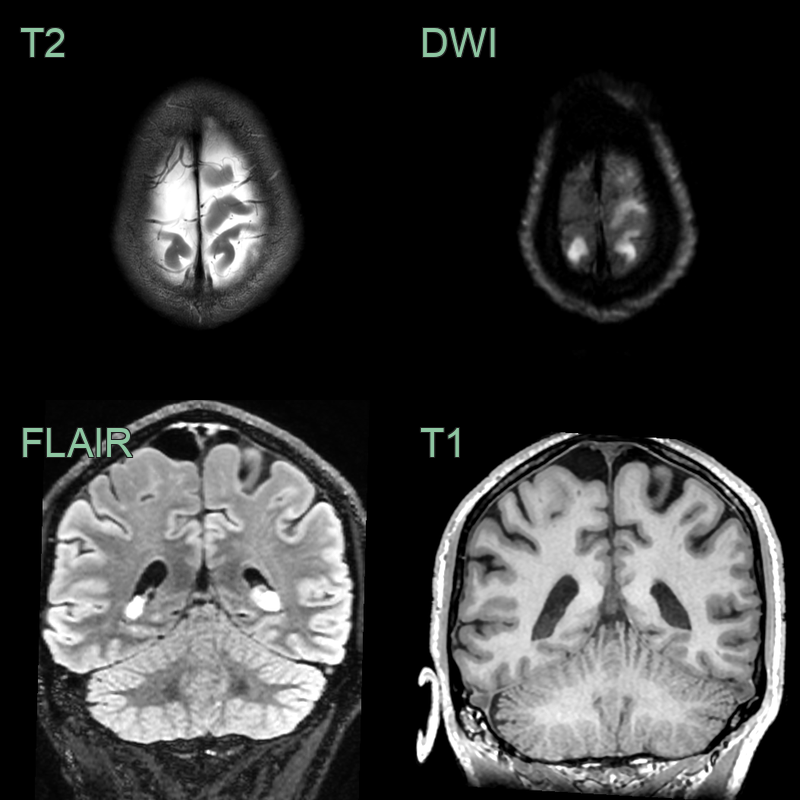

- MRI:

- CSF signal on all sequences (T2 hyperintensity with complete signal suppression on FLAIR)

- No soft tissue or post-gadolinium enhancement

| Epidermoid cyst | Diffusion restriction on MRI; irregular margins |

| Porencephalic cyst | Associated with brain parenchymal injury; communicates with ventricles |